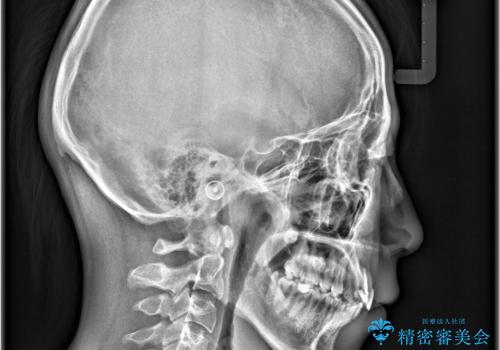

- 「歯のでこぼこを治したい 1年くらいで矯正を終わらせたい」を主訴に来院された患者様です。

叢生量は多く無く歯の傾斜も標準傾斜だったので歯は抜かずにワイヤー矯正で治療を行いました。

左側は2級傾向が強く臼歯の遠心移動をご提案しましたが、1年以内に矯正を終わらせたいという患者様のご意向で希望されず叢生を改善する矯正となりました。